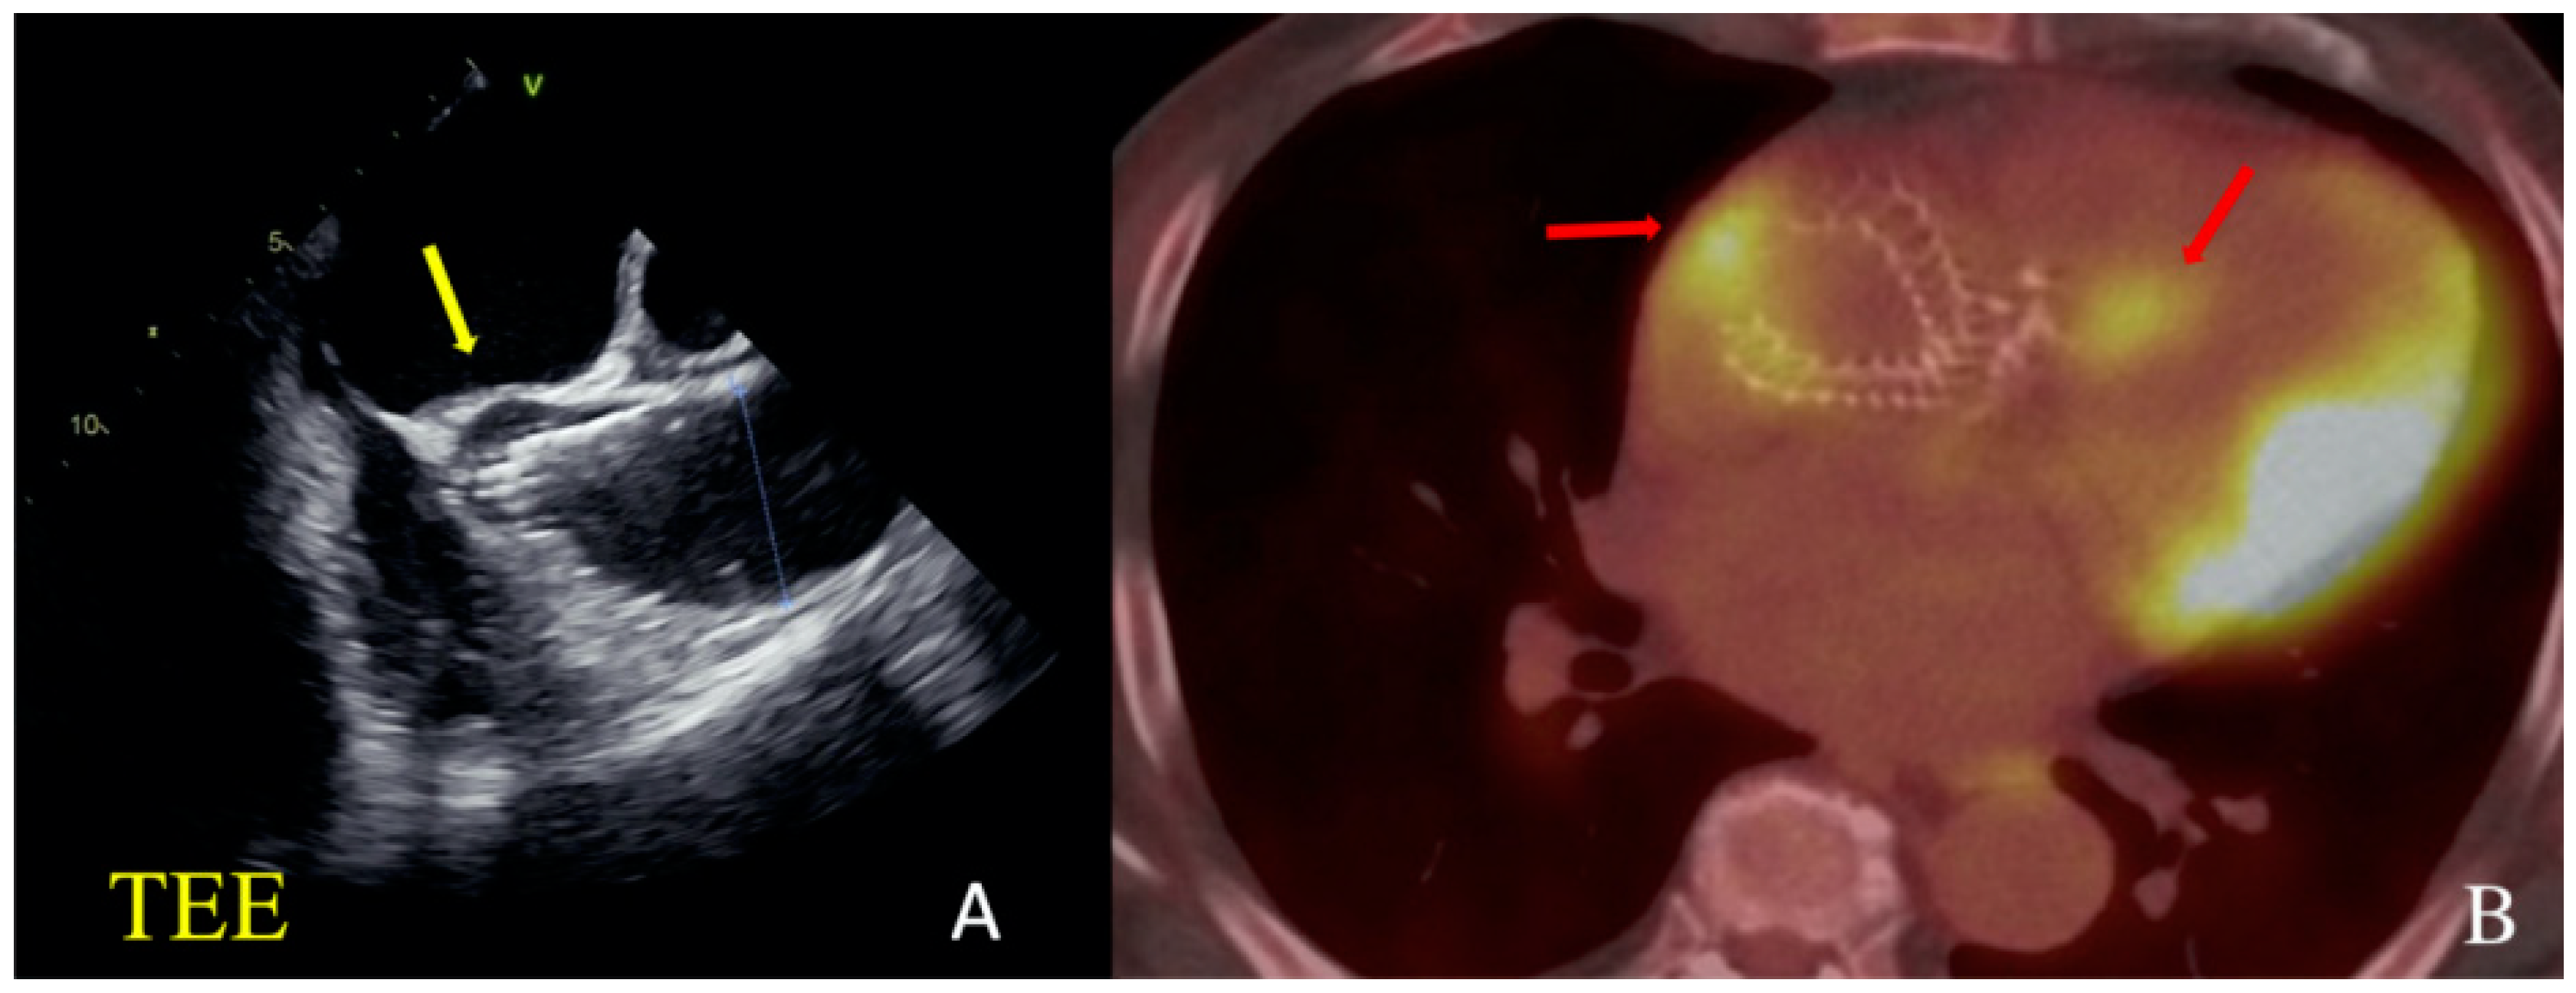

However, on the 10th day after TAVI, the patient noted a deterioration of statement, experiencing a fever of up to 39 °C. According to transesophageal echocardiography (TE-ECHO), a thrombus/vegetation of 6 mm was visualized on the previously implanted valve leaflets. A PET-CT revealed a focus of inflammation on the valve prosthesis and in the area of the non-coronary sinus (Figure 2).

Figure 2.

Clinical Case 1, Patient M., 73 years old. (A) TE ECHO visualization. The yellow arrow indicates a suspected abscess of non-coronary sinus. (B) PET results. The red arrow indicates the zones of hypermetabolism in the area of the valve crown and coronary sinus.